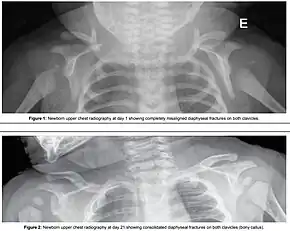

| Shoulder dystocia | |

| Suprapubic pressure being used in a shoulder dystocia | |